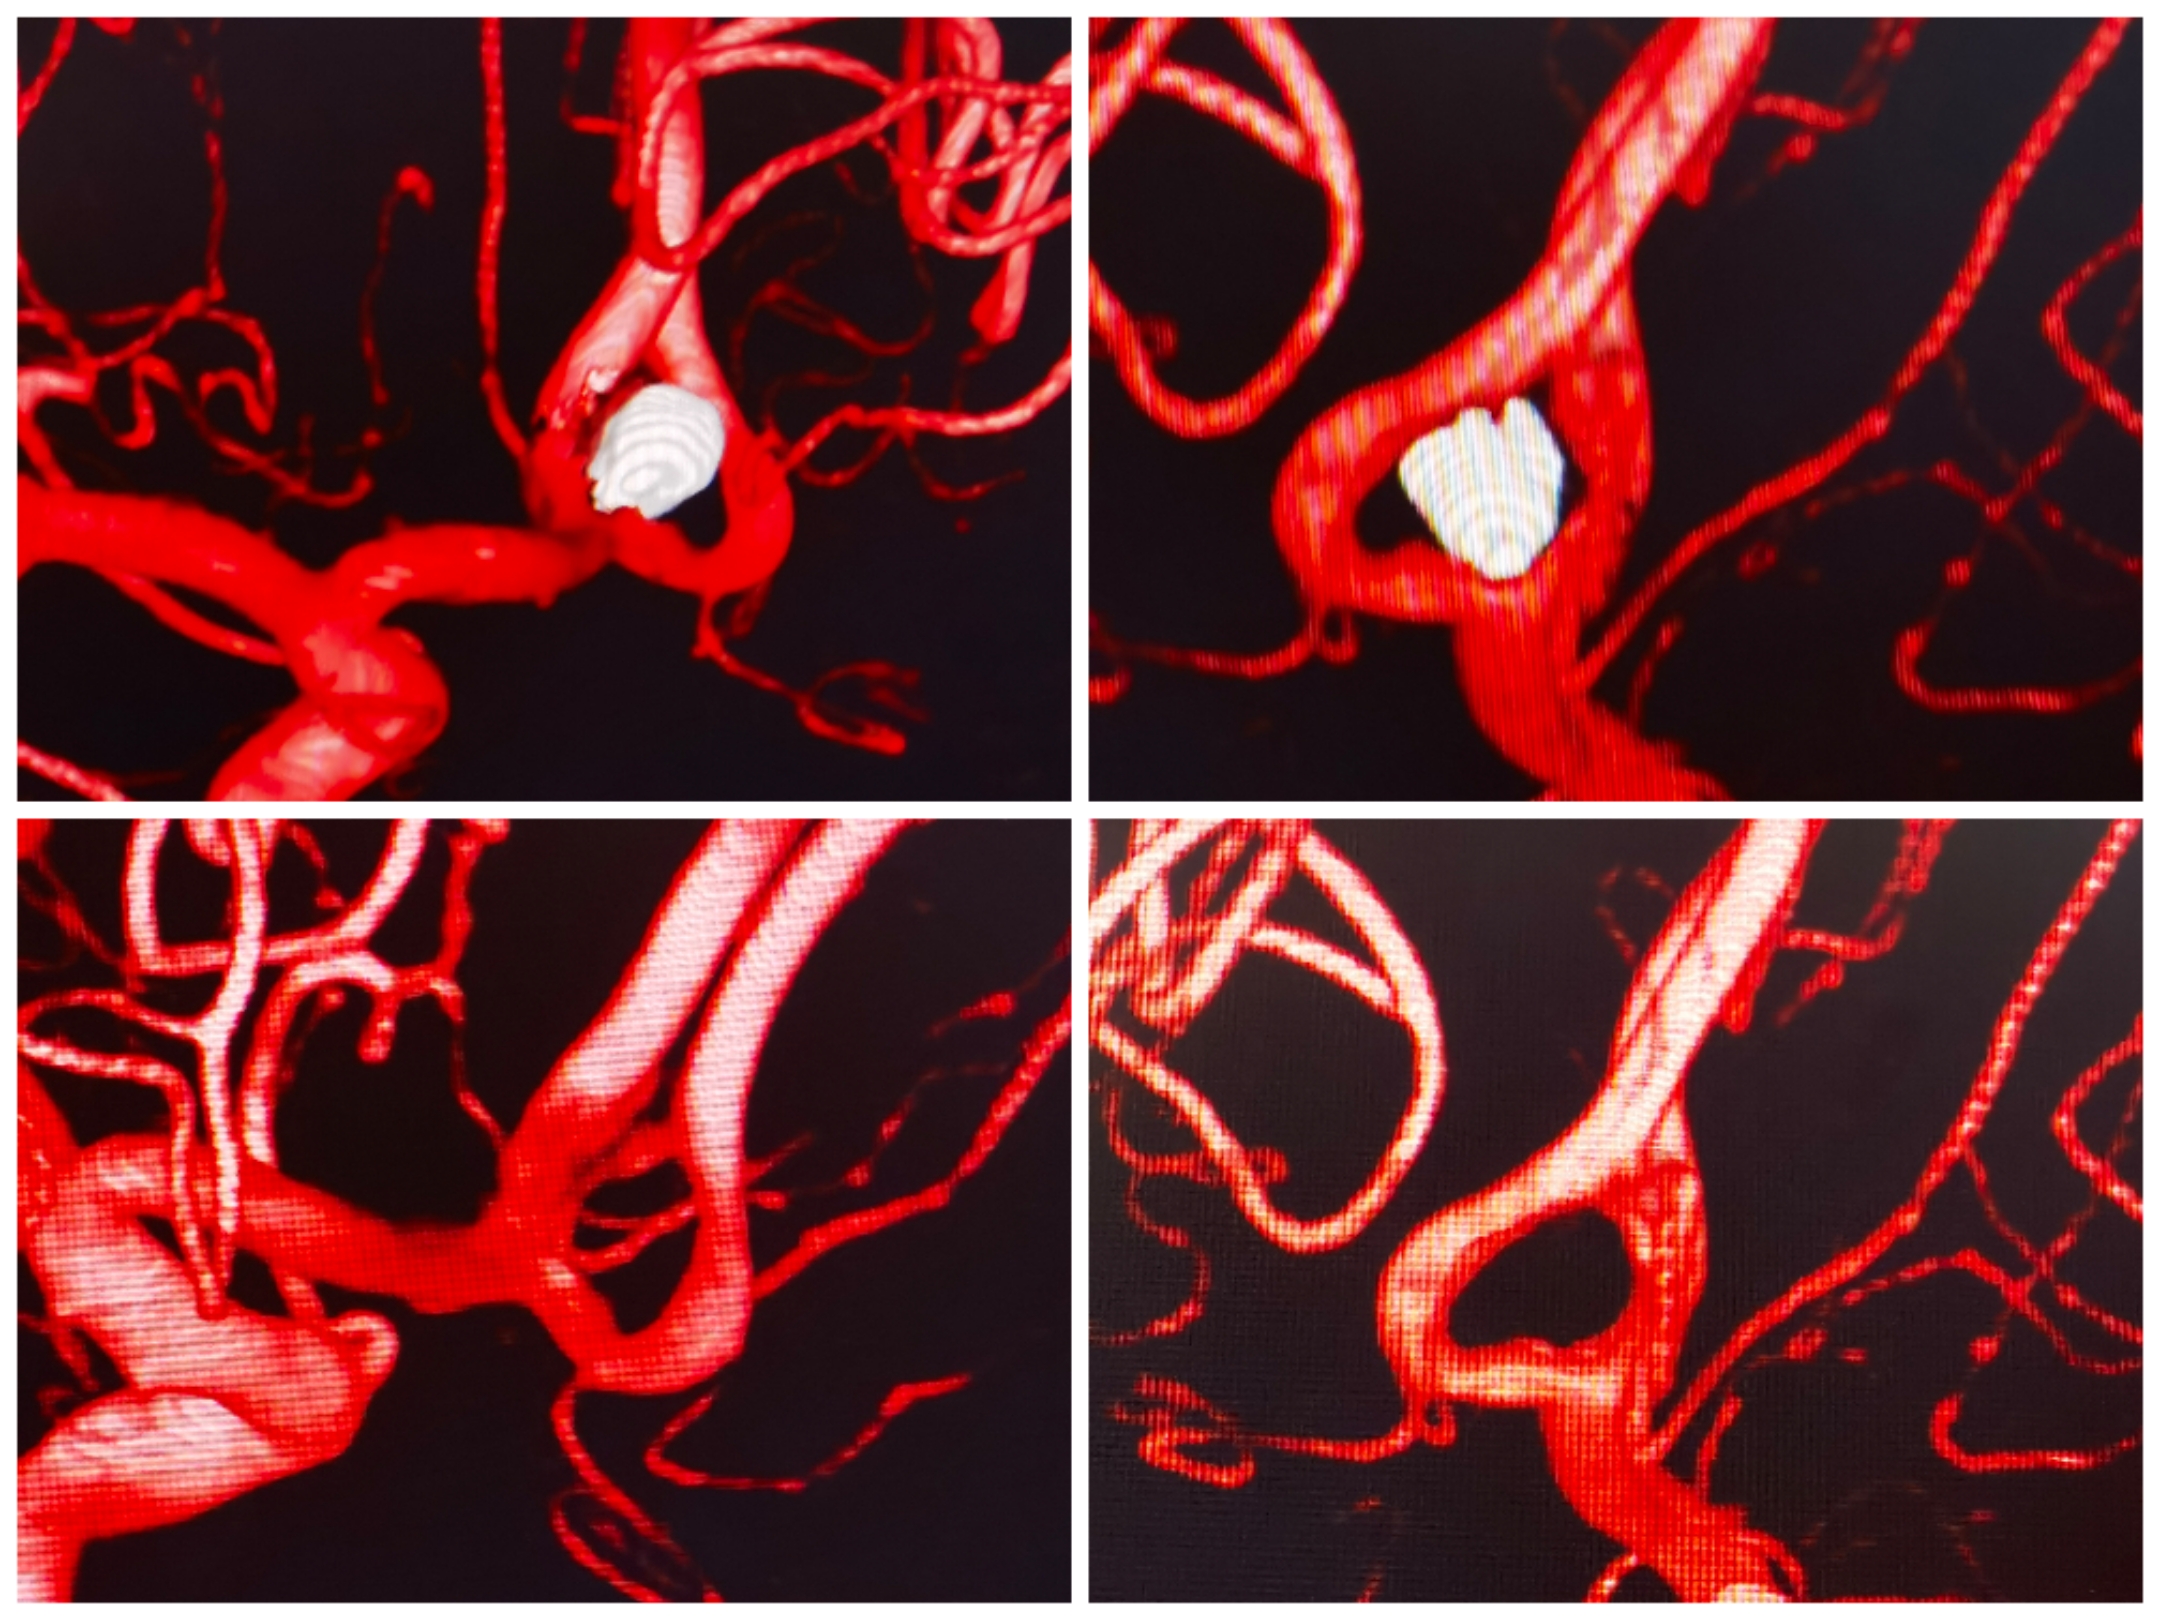

双侧颈内造影

3D重建情况

双微管到达A2后,指引导管造影无法看到动脉瘤。经微管造影及路途,支架导管和栓塞微导管分别到位。选用开环支架穹窿效应缩窄瘤颈,保护对侧大脑前。

栓塞术后情况

术后重建情况